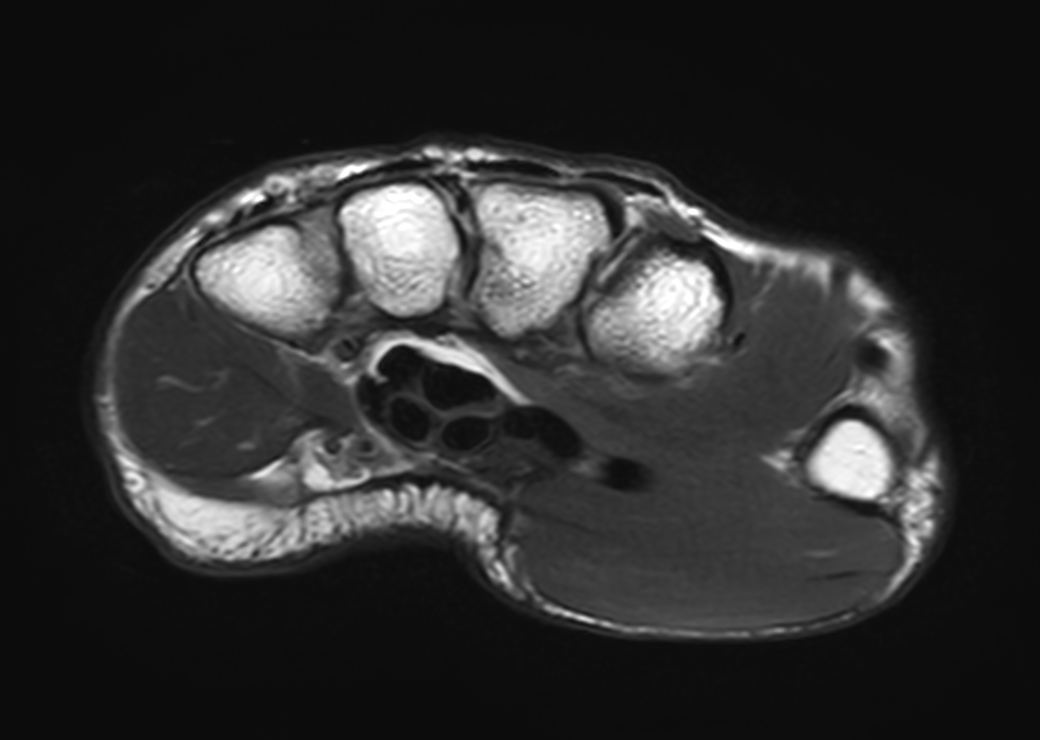

Axial T1w TSE